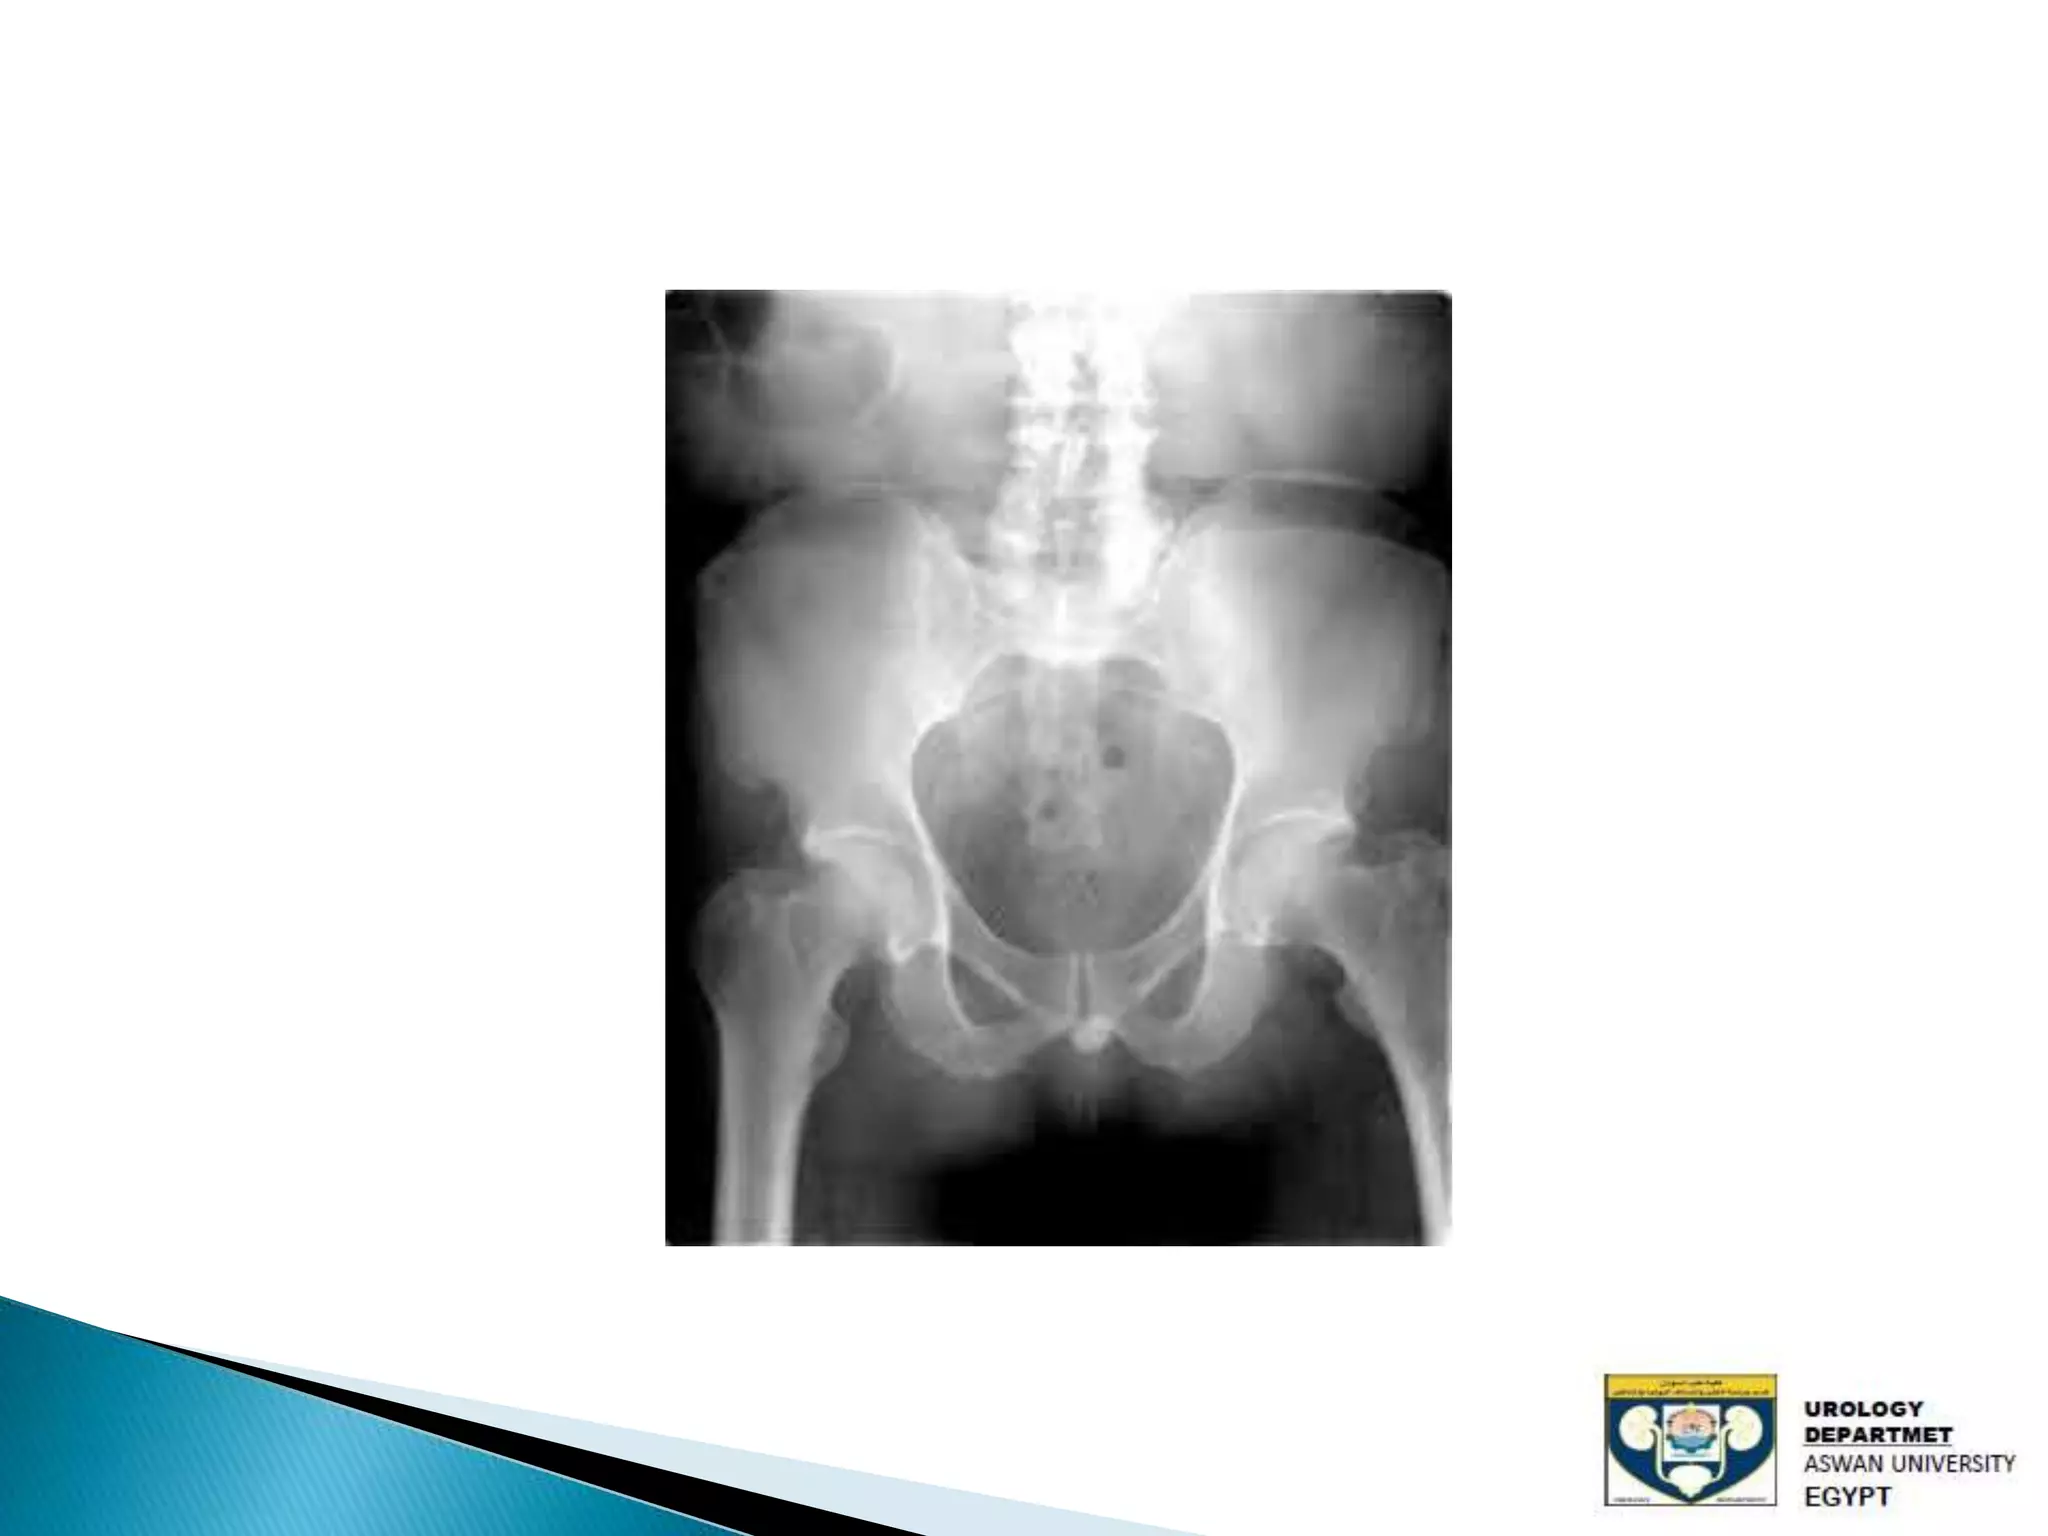

The document discusses urinary tract stones, detailing their types, causes, symptoms, and diagnostic methods. It highlights the risk factors such as infections and obstructions, with men being more commonly affected. Treatment options include various surgical methods, particularly for managing bladder outflow obstruction and lithiasis.